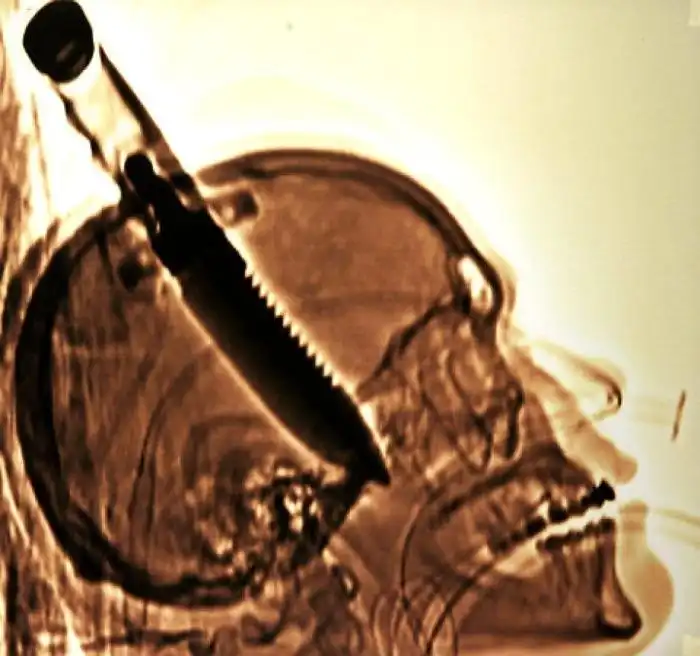

На рентгеновских снимках людей порой можно обнаружить самые необычные предметы, которые находятся в их теле.